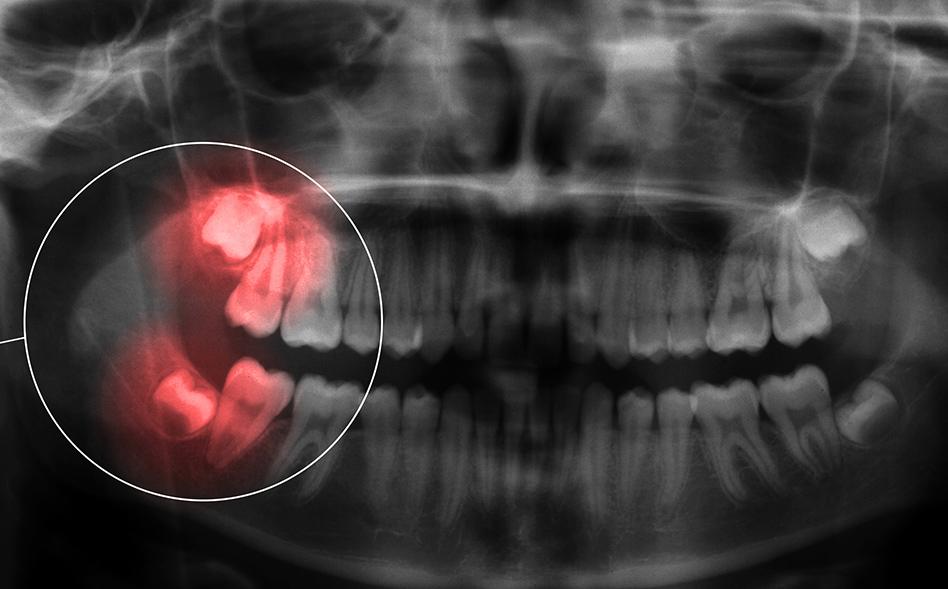

Not all wisdom teeth need extraction, but limited space in the mouth frequently leads to complications such as:

By identifying and treating problems early, we help prevent more serious issues that could compromise your oral health in the future.